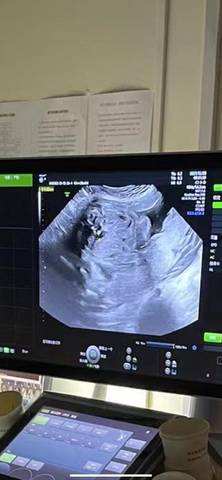

求分析是是公子还是公举

我们是看不出来的,医生也不会明着给你看出来的

你好。我们是判断不了男宝宝跟女宝宝的,孕期定期检查,我觉得宝宝健康就好的。祝心想事成 。

你好,我们都是一样觉得好奇,确实没什么依据,就个惊喜给自己吧,一切顺利!